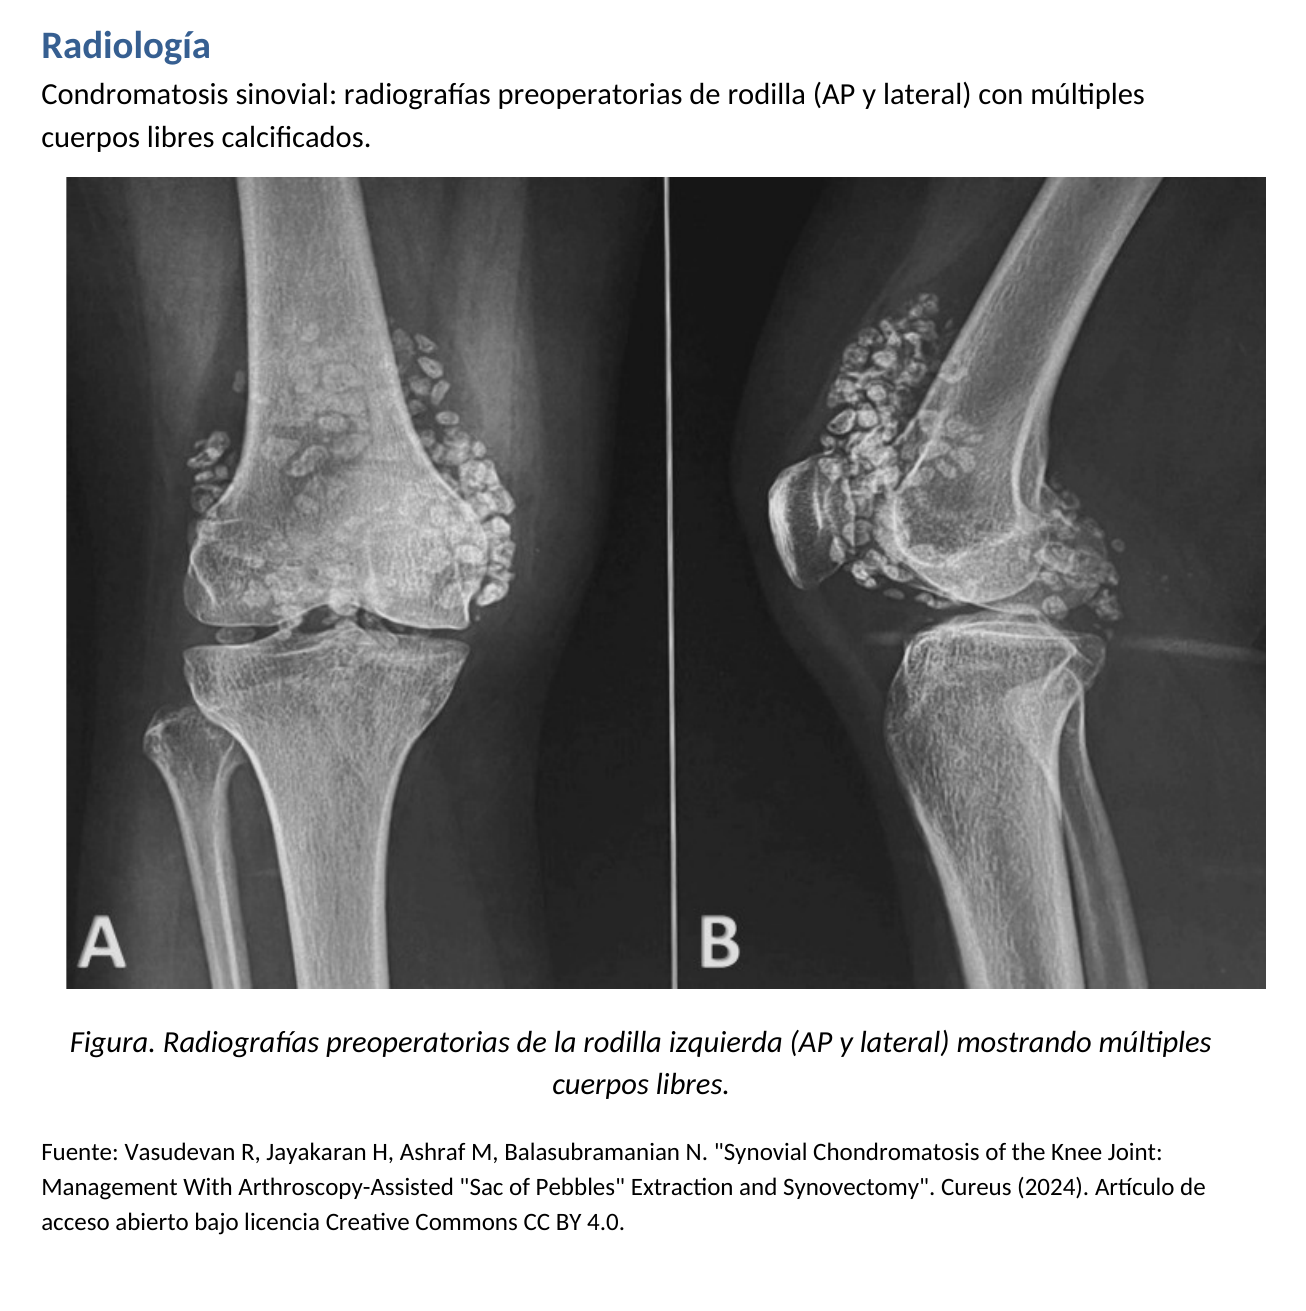

📷 Radiografía

Múltiples cuerpos libres calcificados, a menudo numerosos y relativamente uniformes. En casos evolucionados puede coexistir artrosis secundaria.